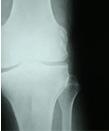

(图:X线下李先生膝关节示意图)

检查结果显示,李先生C-反应蛋白43.15mg/L,血沉120mm/L,RF和ANA均为阴性。膝关节遭受到严重的破坏,关节面边缘模糊不清,凹凸不平或囊状透亮区。